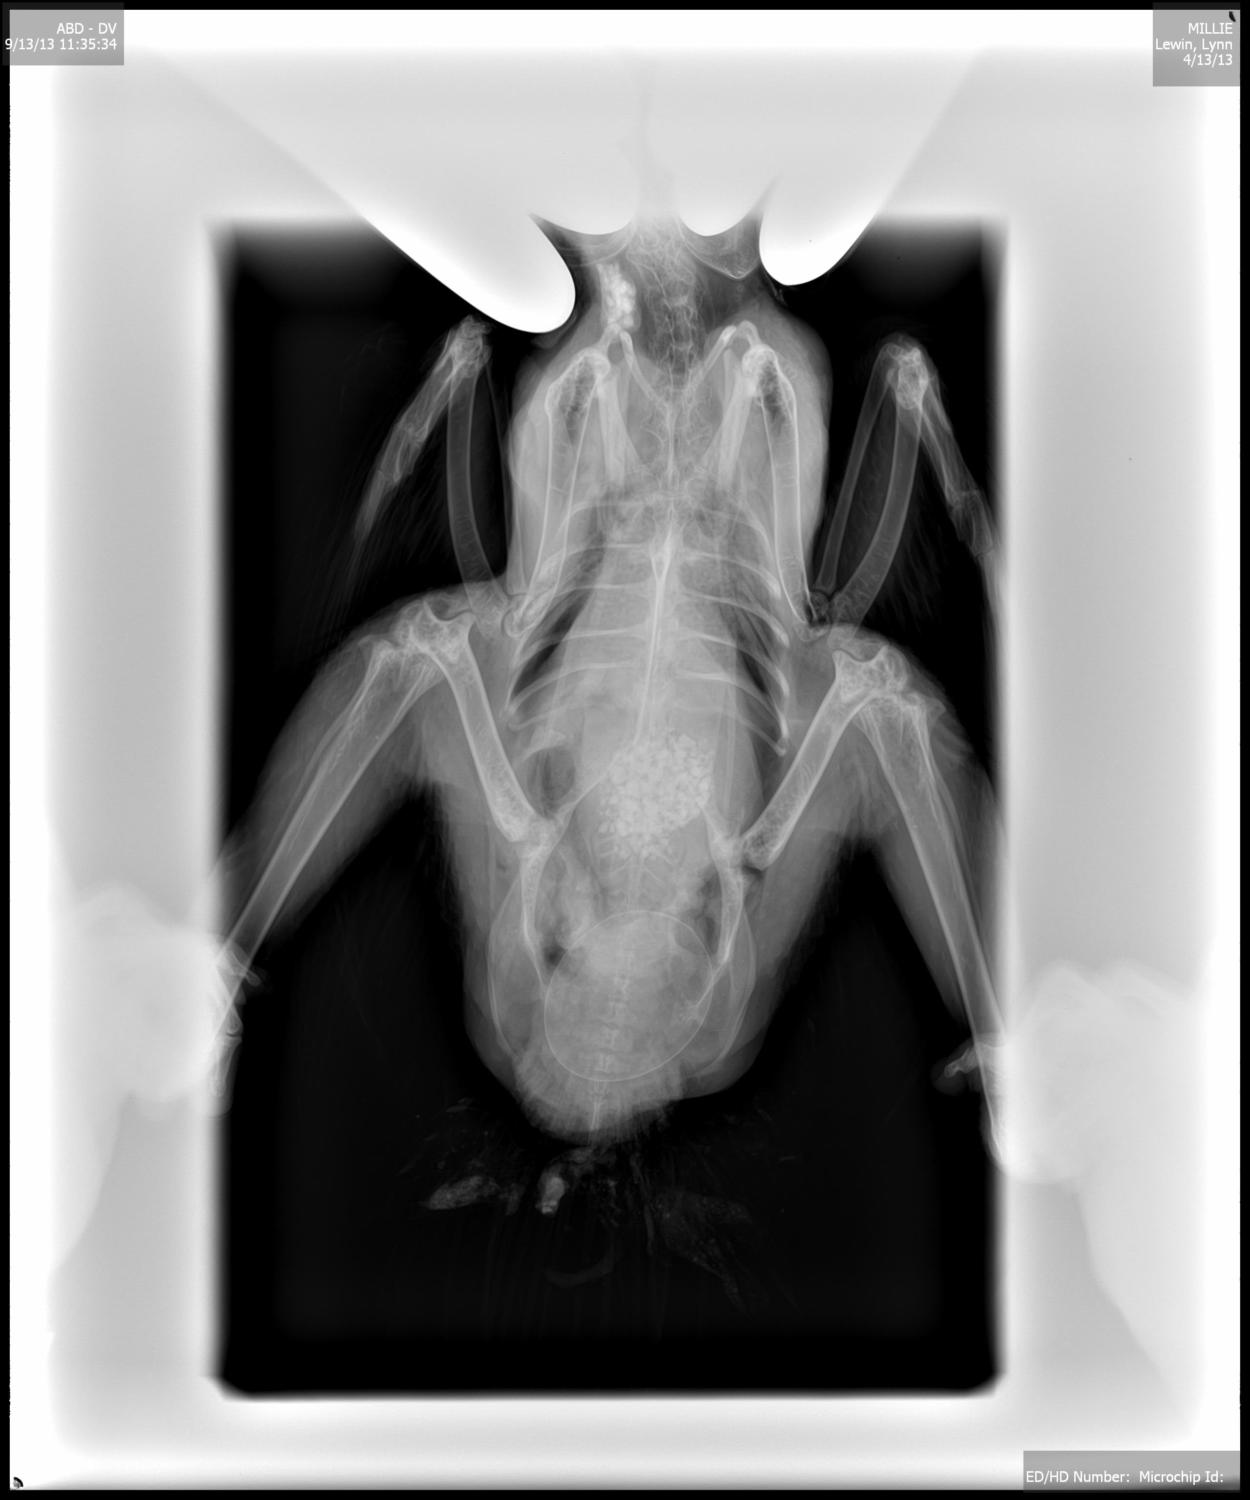

I wanted to post these x-rays of the bound egg in Millie.....so fascinating and as you can tell...that sucker was BIG! No wonder she was in agony.

Oh that poor little chicken. I've been somewhat disappointed at the size of the eggs my chickens lay (so far mediums), but after seeing these x-rays I guess it's a blessing! I'm so glad to hear she continues to improve, and hope she has a full recovery.